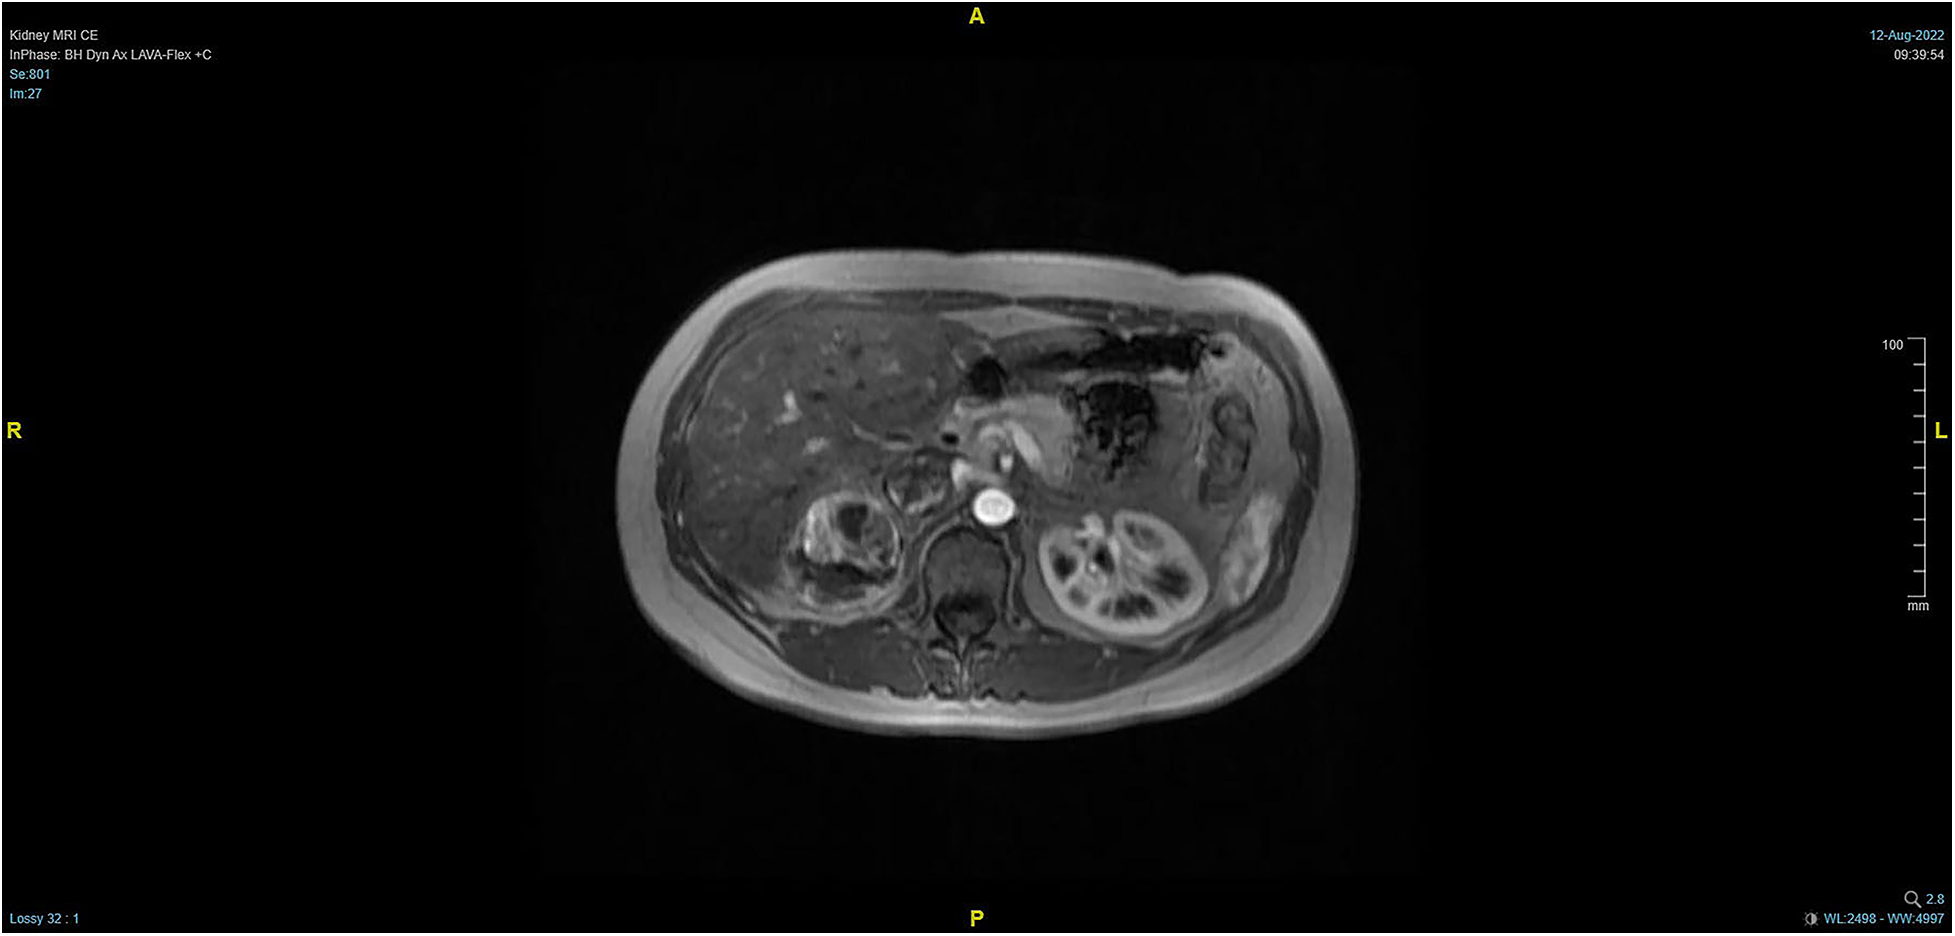

Figure 2

Pre-operative MRI showing that the tumor lesion enlarged upward along the right renal vein into the inferior vena cava (transverse planes).

The patient, a 38-year-old woman, was admitted to the hospital after a physical examination revealed right renal space-occupying lesion for one week. She had no other medical, personal, or family history, other than a history of hamartoma. After admission, the patient underwent the MRI of both kidneys, which revealed an irregularly shaped mass at the upper pole of the right kidney. This mass was characterized by equally short T1 weighted image (T1WI) and T2WI signals, and the signals in the fat-suppression image were not significantly reduced. Multiple cystic components were seen in the mass, some of which were filled with fluid, and the lesion spread into the renal sinus and upward to the inferior vena cava. The right renal veins were not clearly visible. The maximum cross-sectional area of the lesion was about 10.4 × 5.5 cm (coronal). The enhancement scan showed heterogeneity, marked enhancement, separated enhancement, and local clear contour in the delay period. The right kidney was occupied, with multiple cystic variations and hemorrhages in the lesion, and it spread upward along the right renal vein into the inferior vena cava. Malignancy was not ruled out (Figures 1, 2). Urological CT of both kidneys indicated that the right kidney had a space-occupying lesion and that the size and shape of both kidneys were normal.